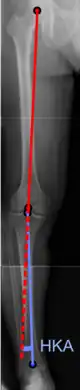

On projectional radiography, the degree of varus or valgus deformity can be quantified by the hip-knee-ankle angle,[7] which is an angle between the femoral mechanical axis and the center of the ankle joint.[8] It is normally between 1.0° and 1.5° of varus in adults.[9] Normal ranges are different in children.[10]

Hip-knee-ankle angle

Hip-knee-ankle angle by age, with 95% prediction interval[10]